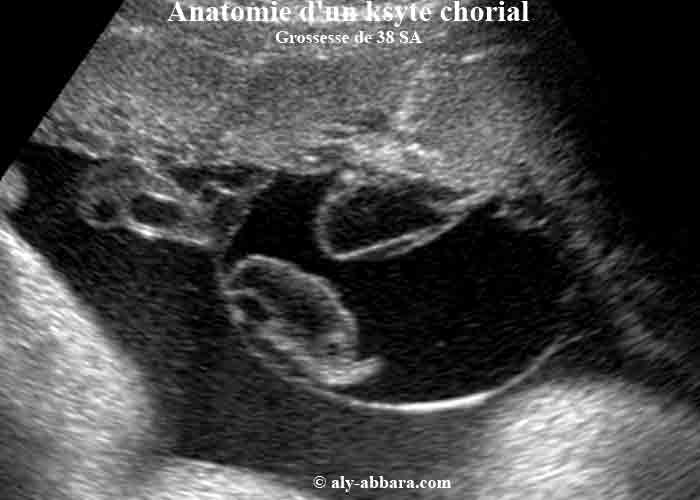

Kyste chorial

Placenta d'une grossesse âgée de 38 semaines d'aménorrhée

Série d'images montrant les éléments anatomiques qui forment un kyste chorial hémorragique évoluant sur la face fœtale du placenta, au niveau de l'insertion du cordon sur ce dernier.

Il s'agit d'un kyste uniloculaire limité d'un côté par l'amnios, et de l'autre côté par la plaque choriale de la face fœtale du placenta ; il mesure 70 x 65 x 45 mm de diamètre ; à l'échographie, son contenu est hypoéchogène avec la présence de deux formations inertes, une détachée et flottante, et l'autre est encore attachée à la plaque choriale, il s'agit de deux vieux caillots organisés.

Un vaisseau sanguin, entre le cordon ombilical et la face f

œtale du placenta, parcourt la paroi amniotique fine du kyste ; une rupture accidentelle in utero de cet amnios, peut se compliquer par la rupture de ce vaisseau et par conséquence, d'une hémorragie fœtale fatale (hémorragie de Benckiser).

L'étude macroscopique de ce kyste, confirme les données échographiques et montre aussi que son contenu est un liquide très sanglante quantifié à (45 cc), en rapport avec une hémorragie ancienne, intrakystique, puis la présence de caillots sanguins fraîchement constitués, au fond du kyste, sur la plaque choriale confirme la survenue d'une hémorragie active et récente. On note l'absence de signes échographiques et du Doppler fœtal en rapport avec une anémie fœtale, et enfin, pas d'anémie chez le nouveau-né, à la naissance.